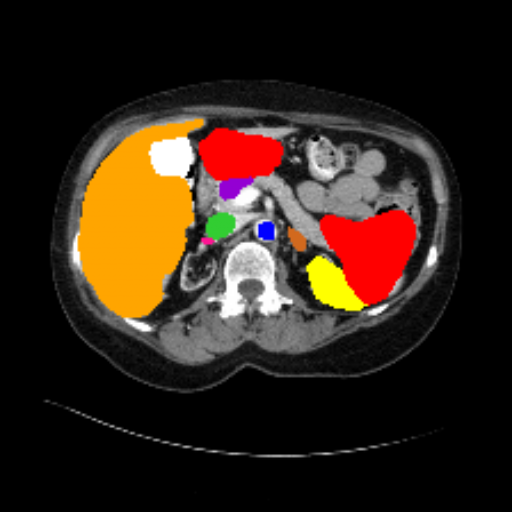

Figure 3 presents a qualitative comparison of segmentation performance on examples from the Synapse, BTCV, ACDC, and ISIC17 datasets. The first two examples (from Synapse) highlight variations in segmentation performance among U-Net, TransUnet, Mamba-Unet, and Swin-Unet. While Swin-Unet performs well in the first example, its performance decreases in the second example, particularly in segmenting the organ highlighted in blue. Additionally, it misclassifies background regions as the class highlighted in orange. In contrast, our approach demonstrates high robustness in segmenting all classes accurately and aligning well with the ground truth masks.

Across BTCV, ACDC, and ISIC17, the comparison methods exhibit varying performance depending on the task and class. For instance, Mamba-Unet struggles to segment multiple organs in BTCV, even misclassifying certain classes as others. In the ACDC dataset, both TransUnet and Mamba-Unet perform poorly in segmenting the three classes. In the last column (ISIC17), Swin-Unet oversegments the skin lesion compared to the ground truth. Unlike the comparison models, our approach consistently delivers effective segmentation across different tasks and datasets.

These qualitative findings further reinforce the quantitative results presented in the experimental section, demonstrating the effectiveness of our MambaCAFU model in handling binary and multi-class segmentation across diverse medical imaging modalities and tasks.

Slice GT Unet TransUnet Mamba-Unet Swin-UMamba MambaCAFU-V1

Figure 3: Visual comparison of segmentation examples from Synapse (first two examples), BTCV (3-4 examples), ACDC (5th example) and ISIC17 (last example). Columns: input slice, ground truth, Unet, TransUnet, Mamba-Unet, Swin-UMamba, and MambaCAFU-V1.